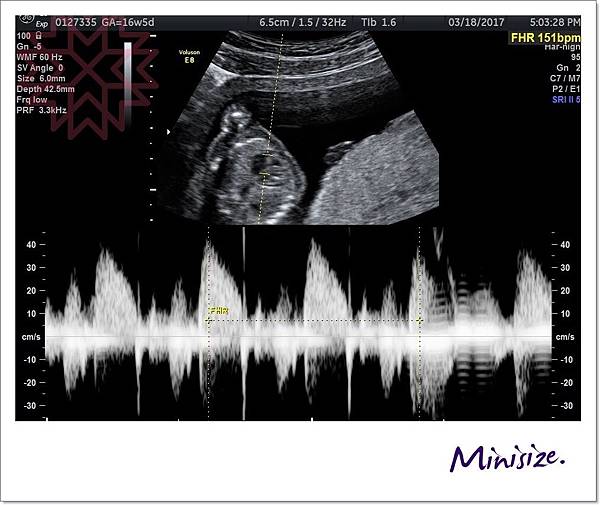

聽到寶寶鏗鏘有力的心跳

真的好感動

小生命正在努力地長大中!